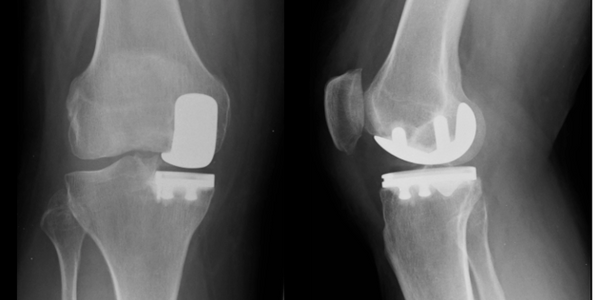

Mr Jawad Sultan is a Consultant Trauma and Orthopaedic Surgeon who specialises exclusively in knee surgery in Manchester. His clinical practice includes partial and total knee replacement, ACL reconstruction, and the management of complex multi-ligament knee injuries.

He has a specialist interest in robotic-assisted knee replacement (MAKO) and patient-specific customised knee replacement (Conformis) for selected patients. Mr Sultan treats the full range of knee conditions including knee arthritis, sports injuries, meniscal tears, patellar instability, and complex knee instability problems. His practice includes both routine and advanced knee surgery, including revision ACL reconstruction, osteotomies around the knee, cartilage restoration procedures and knee ligament reconstruction surgery.